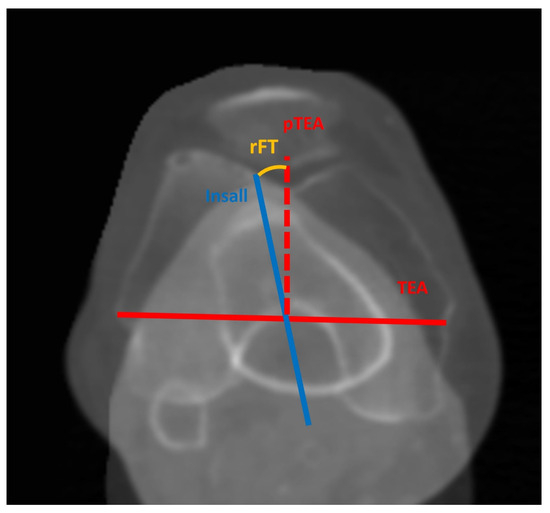

| FMA, ° | 6.1 ± 1.5 (2.6–11.4) |

| CTA, ° | 4.2 ± 1.7 (0.6–8.2) |

| rFT, ° | −6.7 ± 4.7 (−19.1–3.7) |

| HKA-X | 0.99 | 0.98–1.0 |

| aHKA | 0.99 | 0.99–0.99 |

| MDFA | 0.99 | 0.99–1.0 |

| MPTA | 0.99 | 0.98–1.0 |

| FMA | 0.99 | 0.99–0.99 |

| CTA | 0.87 | 0.83–0.90 |

| tF | 0.97 | 0.97–0.98 |

| tT | 0.98 | 0.97–0.98 |

| rFT | 0.93 | 0.91–0.95 |

| LAT | 0.91 | 0.88–0.93 |